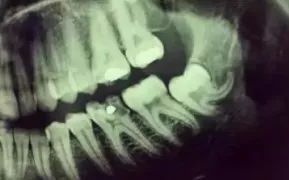

小牙片(根尖片)

主要影相單隻牙齒,可以了解牙齒蛀齒程度,牙根周圍的病變情況,牙周骨質破壞情況等。口腔顎面外科不常用。